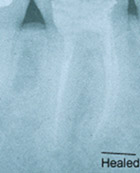

Answer:A root canal is a root filling. It is necessary when the nerve in a tooth is injured and/or dies. A dead nerve sometimes can be seen on an x-ray. This is noted by the dark area at the bottom of the root tips on the first radiograph (x-ray) below. Root canal therapy can be done in one or several visits. A root canal helps an infected tooth heal. During the procedure the inside of the tooth is cleaned and filled. Afterwards, the tooth will need either a filling or a post & core and crown.

The radiograph (x-ray) series below shows an example of the root canal process. This patient initially presented with infection and pain but had immediate relief of symptoms following the first visit. Complete healing is noted on the one-year root canal followup radiograph (x-ray). The healing is evidenced by an absence of a dark area around the root tips, indicating that new bone has grown in the area of previous infection. The very white area inside the roots is the root canal filling material which is gutta percha, a derivative of a South American gum tree. This material is commercially packaged as root canal filling material and is recommended by the University of Connecticut Dental School.